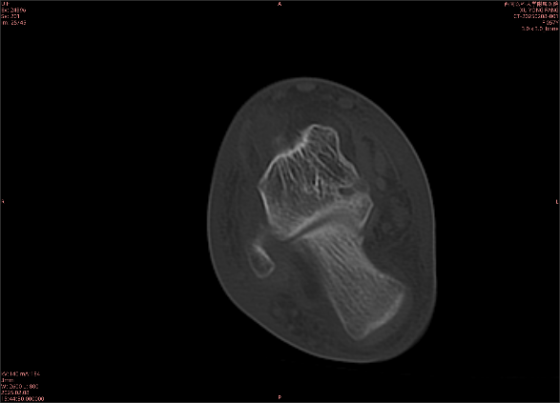

举例图像

图2

专业解释看不懂没关系,大家看图1和图2就可以了,这是同一个患者跟骨的磁共振和CT图像,图1的红色箭头指示的黑线就是磁共振图像显示的骨折线,一目了然。而对比图2的CT图像上并未显示异常。